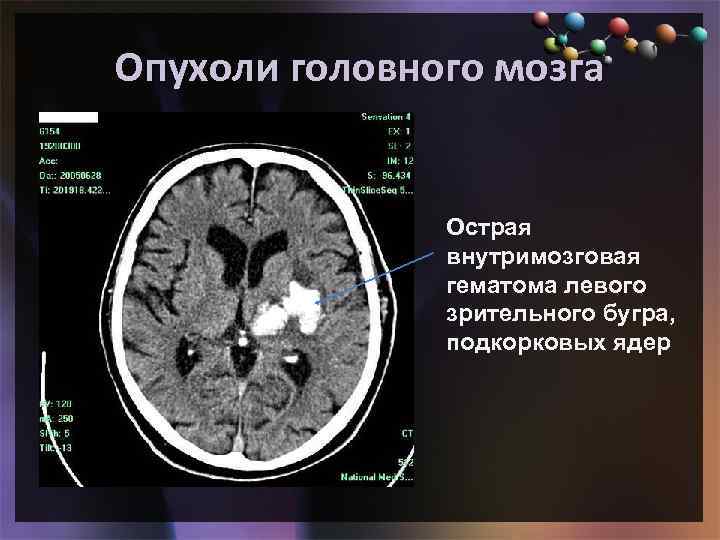

Иллюстрации и пояснения: гиподенсивный очаг на КТ головного мозга

Раздел: Кадры перемен